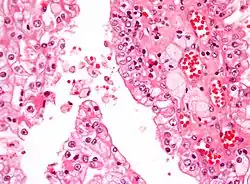

| Micrograph showing the most common type of kidney cancer (clear cell renal cell carcinoma). H&E stain. | |

The most common type of kidney malignancy is renal cell carcinoma,[35] which is thought to originate from cells in the proximal convoluted tubule of the nephron.[15][36] Another type of kidney cancer although less common, is transitional cell cancer (TCC) or urothelial carcinoma of the renal pelvis.[37] The renal pelvis is the part of the kidney that collects urine and drains it into a tube called the ureter.[37] The cells that line the renal pelvis are called transitional cells, and are also sometimes called urothelial cells. The transitional/urothelial cells in the renal pelvis are the same type of cells that line the ureter and bladder. For this reason TCC of the renal pelvis is distinct from RCC and is thought to behave more like bladder cancer.[37] Other rare types of kidney cancers that can arise from the urothelial cells of the renal pelvis are squamous cell carcinoma and adenocarcinoma.[15]